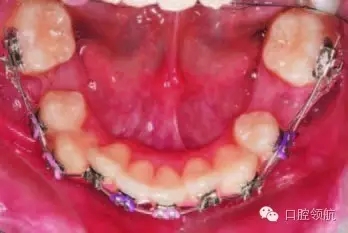

尖牙代替?zhèn)惹醒赖姆椒ǎ和ㄟ^(guò)正畸方法將尖牙移動(dòng)到側(cè)切牙的位置,再經(jīng)局部漂白、調(diào)磨改形或全冠修復(fù),恢復(fù)側(cè)切牙形態(tài)。正畸醫(yī)生要考慮的問(wèn)題有:尖牙與切牙齦緣高度是否一致,尖牙是否需要腭側(cè)控根。通過(guò)直接粘結(jié)具有根腭向轉(zhuǎn)矩的托槽,或者將具有根唇向轉(zhuǎn)矩的托槽反粘,配合使用全尺寸弓絲(0.021英寸×0.025 英寸),以實(shí)現(xiàn)尖牙的腭側(cè)控根(圖3.5)。對(duì)牙尖的調(diào)磨應(yīng)逐次進(jìn)行,以最大限度地減少對(duì)牙髓的刺激,避免出現(xiàn)牙髓鈣化或失活。